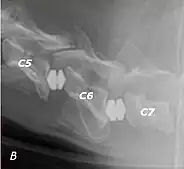

Wobbler disease is probably inherited in the Borzoi, Great Dane, Doberman, and Basset Hound.[2] Instability of the vertebrae of the neck (usually the caudal neck) causes spinal cord compression. In younger dogs such as Great Danes less than two years of age, wobbler disease is caused by stenosis (narrowing) of the vertebral canal[3] related to degeneration of the dorsal articular facets and subsequent thickening of the associated joint capsules and ligaments.[1] A high-protein diet may contribute to its development.[4] In middle-aged and older dogs such as Dobermans, intervertebral disc disease leads to bulging of the disc or herniation of the disc contents, and the spinal cord is compressed.[3] In Great Danes, the C4 to C6 vertebrae are most commonly affected; in Dobermans, the C5 to C7 vertebrae are affected.[5]

The disease tends to be gradually progressive. Symptoms such as weakness, ataxia, and dragging of the toes start in the rear legs. Dogs often have a crouching stance with a downward flexed neck. The disease progresses to the front legs, but the symptoms are less severe. Neck pain is sometimes seen. Symptoms are usually gradual in onset, but may progress rapidly following trauma.[6] X-rays may show misaligned vertebrae and narrow disk spaces, but it is not as effective as a myelogram, which reveals stenosis of the vertebral canal. Magnetic resonance imaging has been shown to be more effective at showing the location, nature, and severity of spinal cord compression than a myelogram.[7] Treatment is either medical to control the symptoms, usually with corticosteroids and cage rest, or surgical to correct the spinal cord compression. The prognosis is guarded in either case. Surgery may fully correct the problem, but it is technically difficult and relapses may occur. Types of surgery include ventral decompression of the spinal cord (ventral slot technique), dorsal decompression, and vertebral stabilization.[8] One study showed no significant advantage to any of the common spinal cord decompression procedures.[9] Another study showed that electroacupuncture may be a successful treatment for Wobbler disease.[10] A new surgical treatment using a proprietary medical device has been developed for dogs with disc-associated wobbler disease. It implants an artificial disc (cervical arthroplasty) in place of the affected disc space.[11]

Wobbler disease is definitively diagnosed by x-ray, nuclear scintigraphy or bone scan. X-rays will show channel widening or filling the easiest and are often most cost-effective to horse owners. X-rays will also show any structural anomaly, arthritis, facet remodeling, or bone spurs present. Preliminary diagnosis can be made by ultrasound but x-rays are needed to measure the true depth of facet involvement. For extent of damage to associated structures, veterinarians may opt to have the horse undergo a bone scan or nuclear scintigraphy.